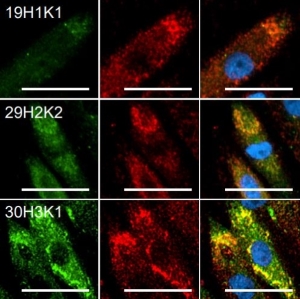

Then, to our pleasant surprise, we saw the researchers cited our cells in another BBB related publication. This time, the investigators looked into some of the mechanisms behind neuroinflammation seen in ischaemic stroke and other disorders. They found that inhibition of Rho kinase neutralized the disruptive effects of TNF-α on BBB integrity. You can read the full study here.